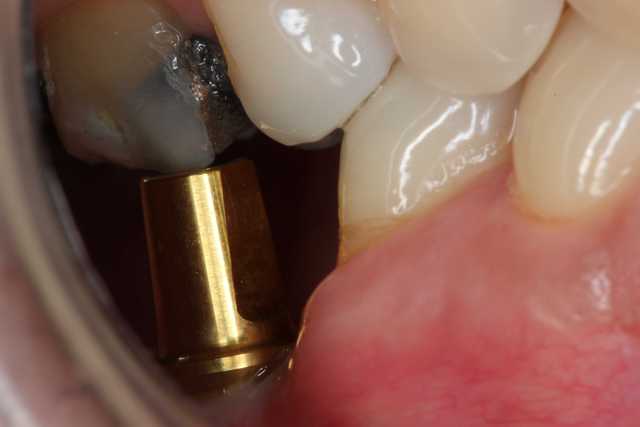

Voici le cas :

Patient classe III sportif musclé, crête étroite.

L'implant, un Biomet 3i 4,3mm a été posé en 46 par mon correspondant.

Le hic, selon moi, compte tenu du type morpho du patient est la transmission des forces de mastication avec risque de fracture de l'implant. Et ce d'autant plus qu'il y a une petite cratérisation et que par conséquent l'implant n'est pas entièrement enfoui.

Un autre implant est prévu en 47 mais le patient attend pour des raison budgétaires